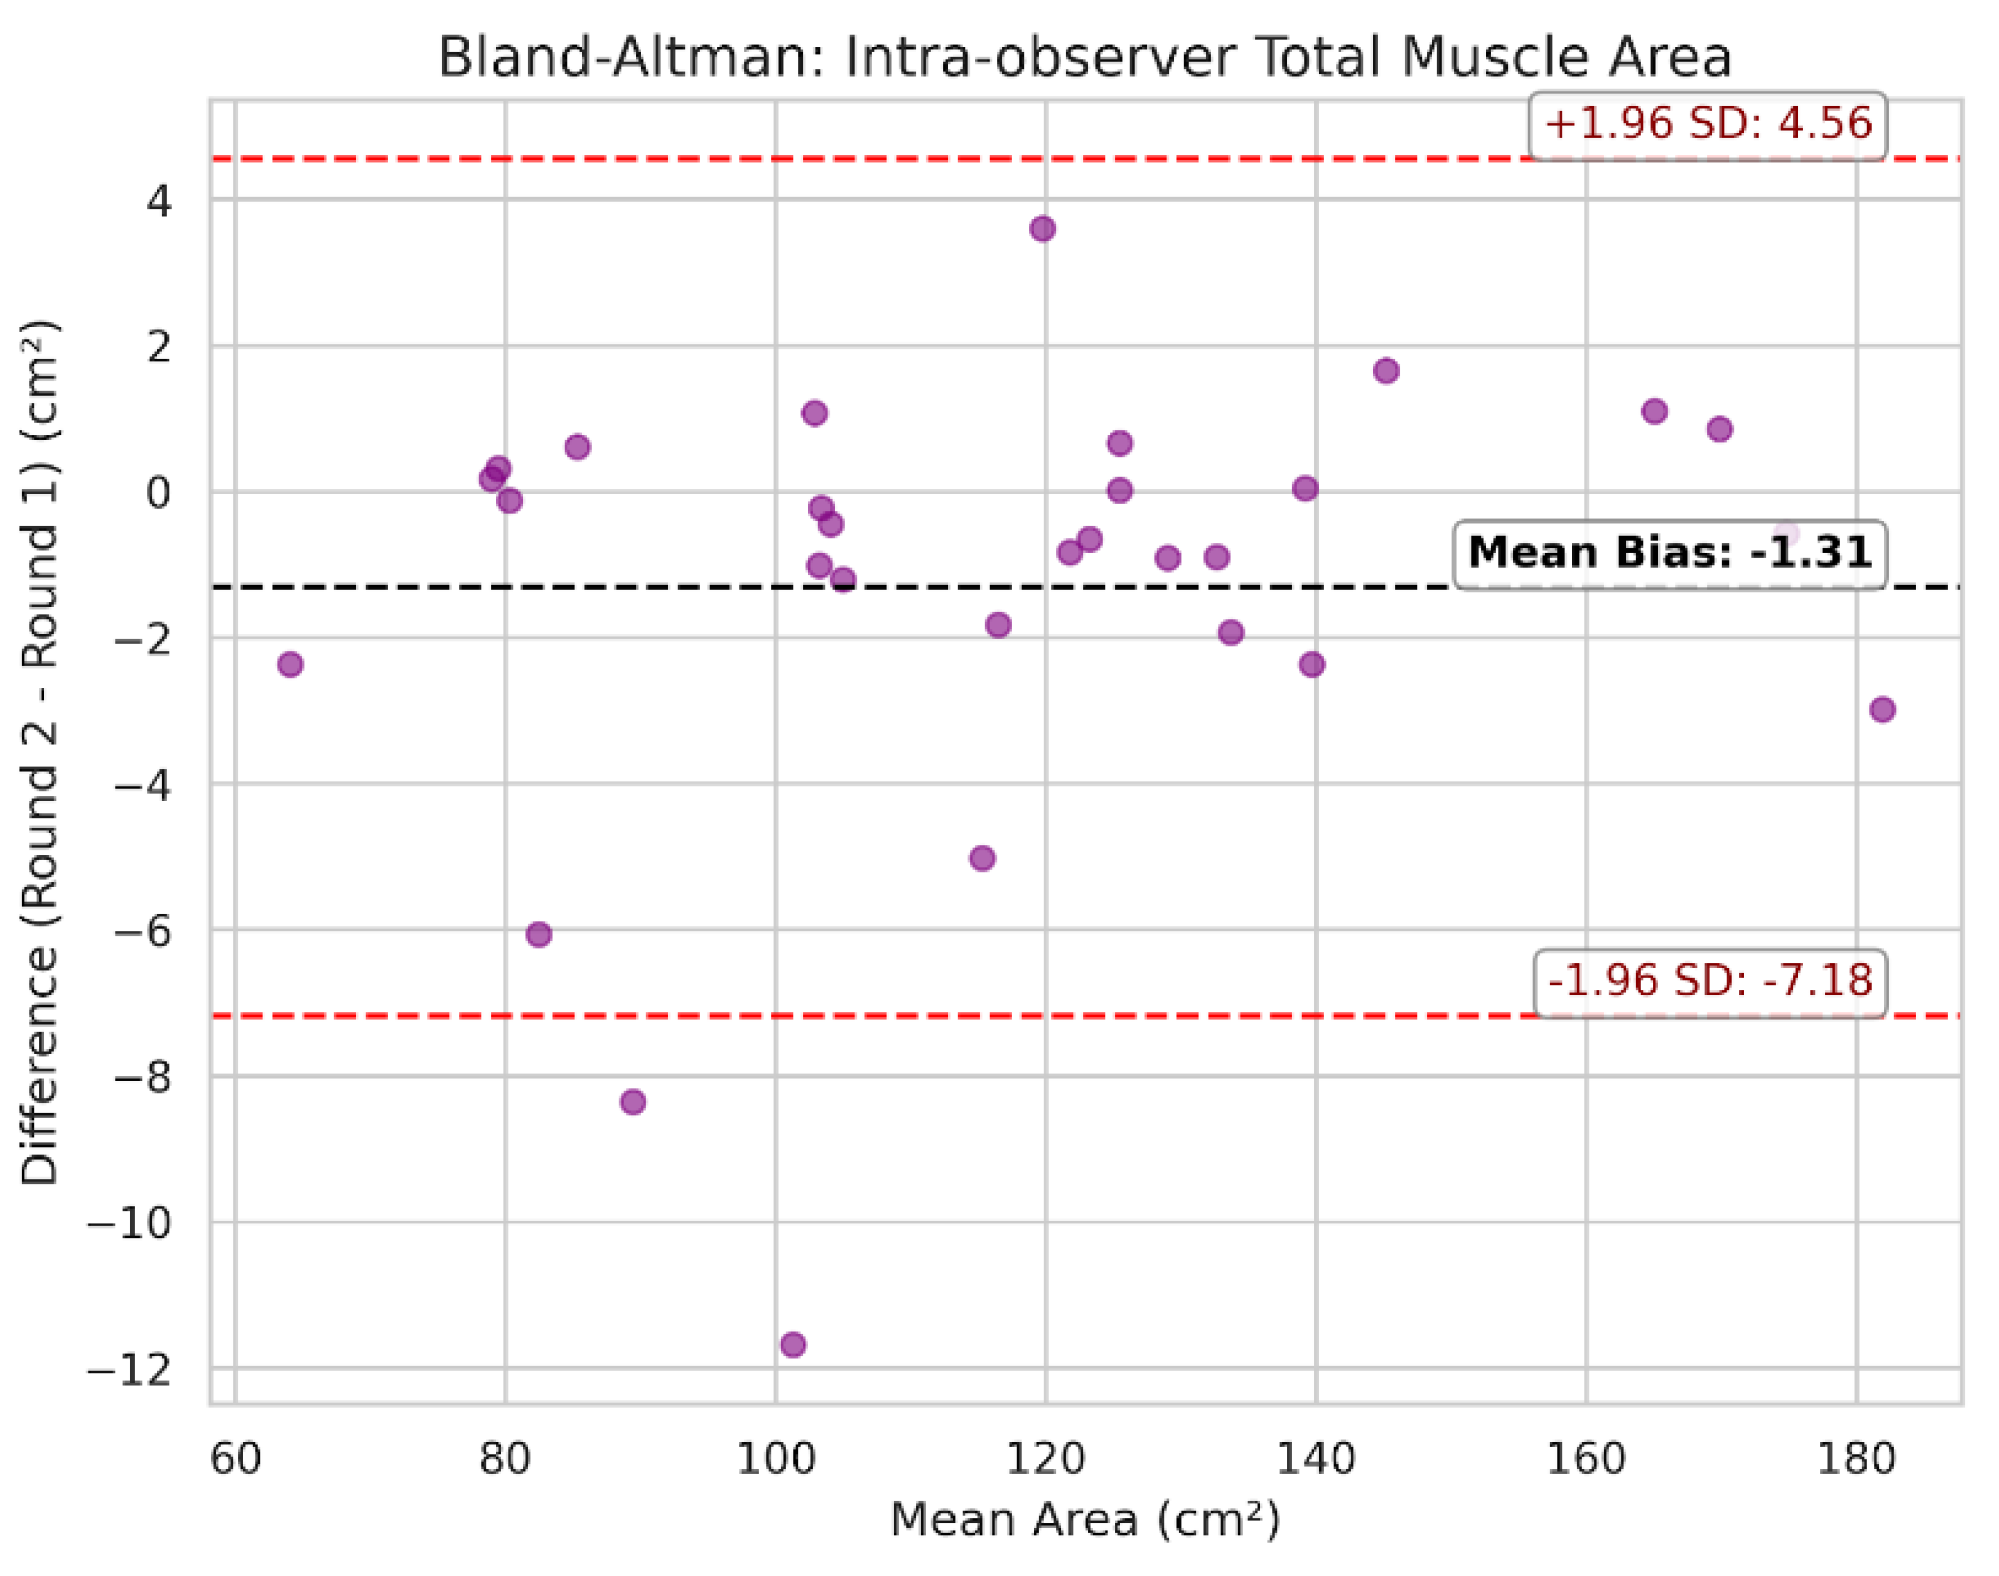

3.4. Intra-Observer Reliability and Time Efficiency

| Metric | Pearson r | MAE | Mean bias (round 2 - round 1) |

|---|---|---|---|

| Total muscle area (cm²) | 0.995 | 1.98 | -1.31 |

| Total mean attenuation (HU) | 0.995 | 0.74 | +0.56 |